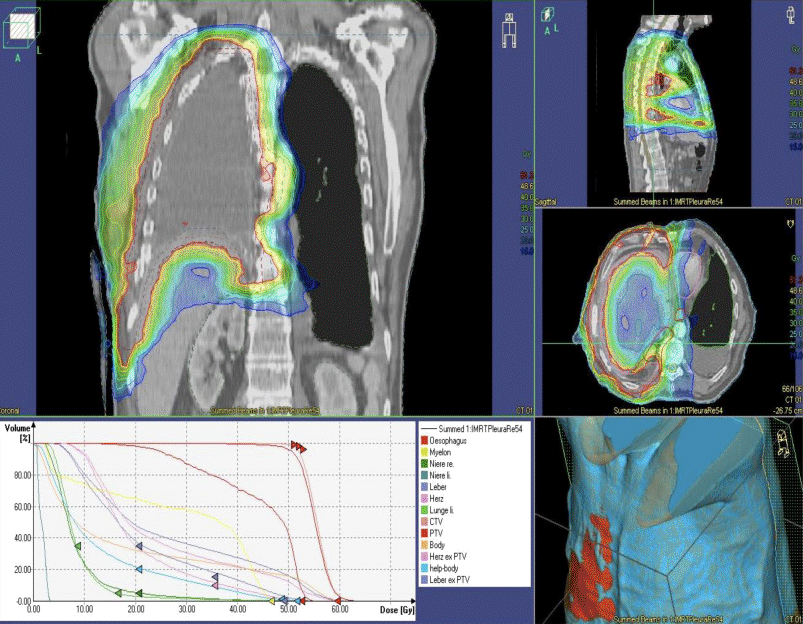

Postoperative hemithoracic irradiation is regarded as part of the three modality treatment concept which combines chemotherapy, operation, and radiotherapy for resectable malignant pleural mesothelioma. The dose of 50–54 Gy should be applied with a once daily fraction of 1.8–2.0 Gy (Fig. 1).

Fig. 1

Postoperative situs after extrapleural pneumonectomy of the right lung and pleura. Intensity-modulated radiotherapy dose plan. Coronal, sagittal, and axial image of the isodose plan. Steep dose fall to the remaining left lung, liver, and kidney

Other fractionation schedules for 3D-conformal radiotherapy are recommended as 25 × 1.8 Gy (45 Gy) to the hemi thorax, followed by a boost onto the high-risk area with 7 × 1.8 Gy (12,6 Gy); or as another alternative 23 × 2 Gy (46 Gy) to the hemithorax, followed by 5 × 2 Gy boost which totals to 56–58 Gy for the high-risk area. In case of IMRT 26 × 1.75 Gy (45.5 Gy) with an integrated boost of 26 × 2.15 Gy (55.9 Gy) are possible [21].

Dose constrains to the organs at risk (OAR; as the non-involved lung, esophagus, spinal cord, liver or gastrointestinal organs, kidneys) have to be respected to avoid acute and long-term side effects as e. g. esophagitis and pneumonitis.